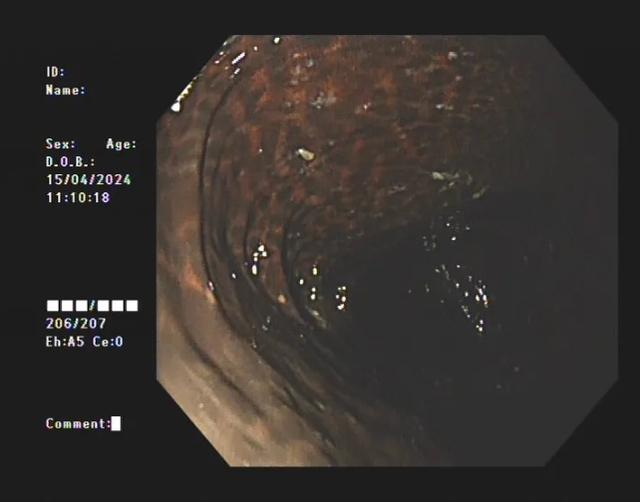

此时,整条肠子变黑、布满斑点,

像“豹纹”一样……

图源:淮安市中医院

直到2024年4月中旬,季女士发现所有的通便茶都不管用了,腹部持续胀痛,这才匆匆赶到淮安市中医院肛肠科就诊。不查不知道,一查吓一跳!患者整条大肠内壁呈现棕黑色蛇皮样的改变,黑色素沉着明显,诊断为“结肠黑变病”,若继续发展,有癌变的可能。

据医生介绍,临床上许多患者自行口服药物后筛查肠镜均有不同程度的结肠黑变病。正常的结肠黏膜就像我们的口腔黏膜一样,是淡红色的,看起来光滑平坦,黏膜表面的小血管纹理清晰可见。而结肠黑变病的肠黏膜色泽呈现棕色、褐色,有豹纹或者蛇皮一样的条状纹,严重的甚至会变成黑色。

结肠黑变病患者的肠道。图源:淮安市中医院

此时,整条肠子变黑、布满斑点

像“豹纹”一样

不查不知道,一查吓一跳!患者整条大肠内壁呈现棕黑色蛇皮样的改变,黑色素沉着明显,诊断为“结肠黑变病”,若继续发展,有癌变的可能。

结肠黑变病患者

结肠黑变病是因为结肠壁的吞噬细胞吞噬了褐色素样物质,导致肠壁色素沉着。通俗点说,就是大肠吃多了色素,就变成了黑肠。此外,直肠前突、肠套叠、溃疡性结肠炎等其他疾病也可能导致黑变病。

季女士整条大肠内壁

呈现出棕黑色蛇皮样

黑色素沉着明显

被诊断为"结肠黑变病"

而结肠黑变病的肠黏膜色泽呈现棕色、褐色,有豹纹或者蛇皮一样的条状纹,严重的甚至会变成黑色。